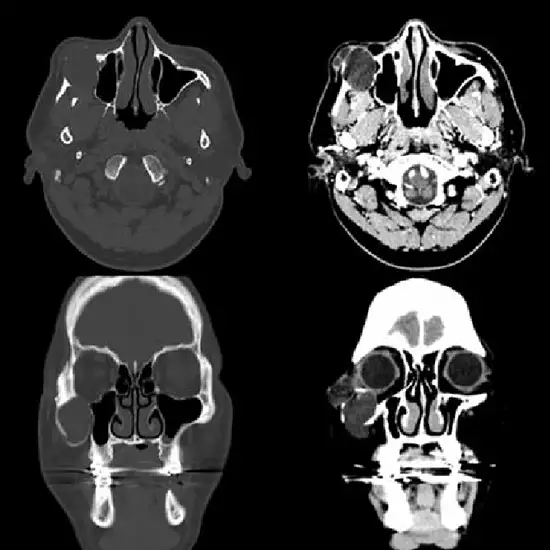

A CT of the Facial Bones is a procedure that produces images of the facial bone structure, including the jaw, nose, eye sockets, and cheekbones, in very thin slices (2-3.5mm). These photographs aid in the diagnosis of facial trauma and malformations.

Your physician has ordered a computed tomography (CT) scan of your facial bone. CT scans create detailed images of the body using X-ray technology and advanced computer analysis. A CT scan of your facial bones can assist your doctor in determining the source of symptoms such as headaches, seizures, dizziness, or swelling. It can also be used to investigate other potential issues, such as those caused by an injury or a tumour.